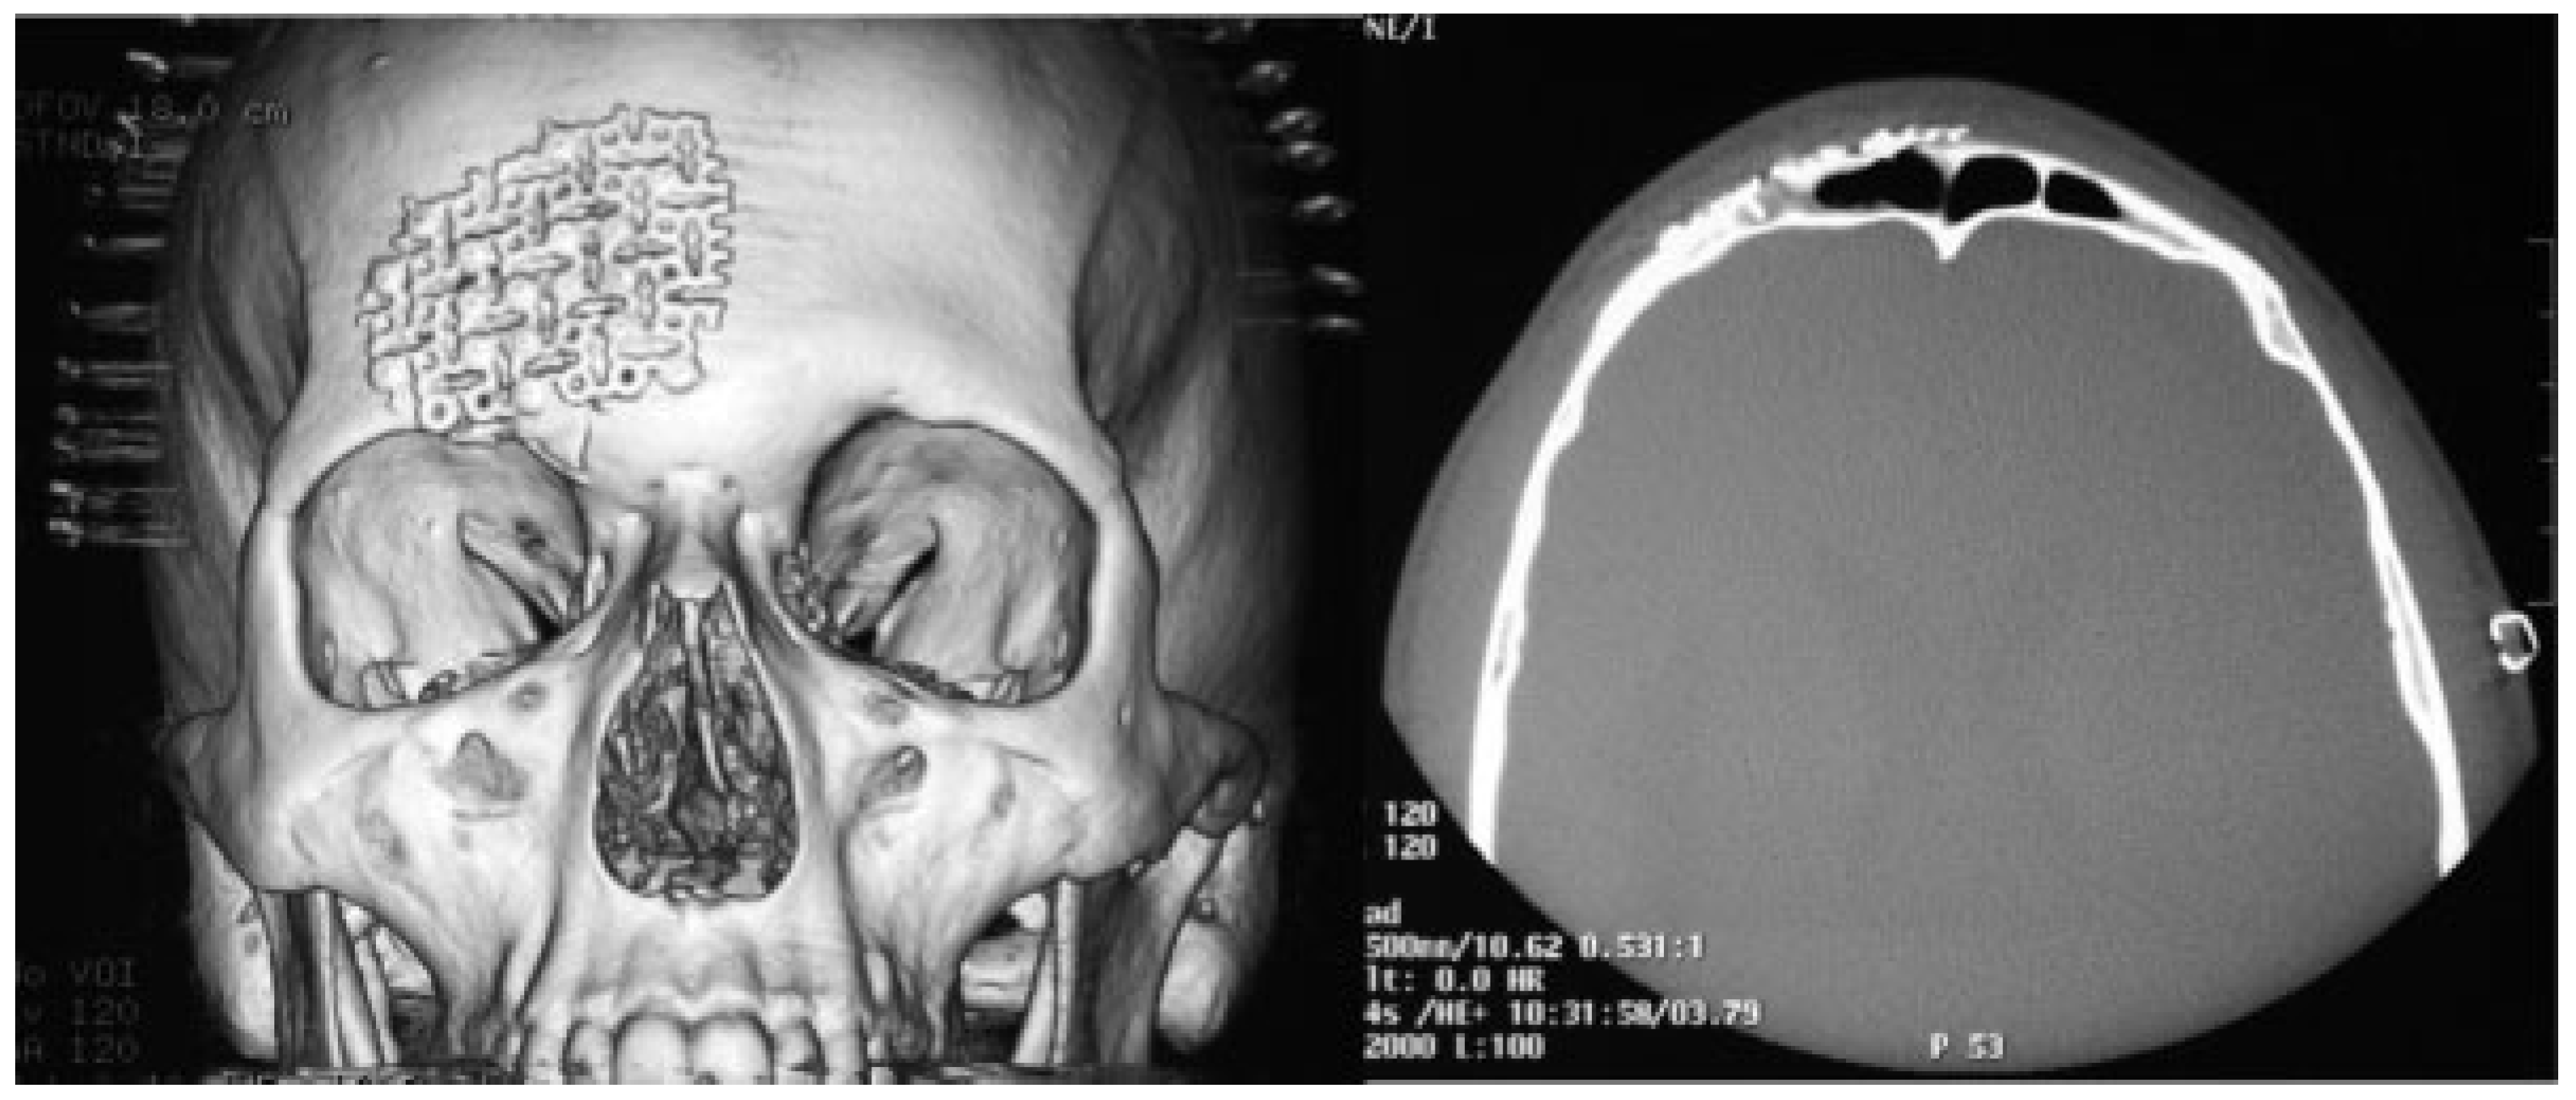

All patients underwent preoperative and postoperative computed tomography (CT) with three-dimensional (3D) reconstruction. The average clinical observation time was 12 months (Figure 1).

3D CT is the gold standard for the examination of facial fractures; it allows visualization of the degree of frontal sinus fracture and precise planning of surgical correction [3,4]. Most injuries in our sample resulted from traffic accidents, and all surgeries were performed within 3 weeks of injury. Surgery to reduce, reconstruct, and fix the fracture was performed under general anesthesia and patients received antibiotics to prevent infection associated with fracture and surgery even for closed anterior table frontal sinus fractures for 2 weeks from diagnosis [5].

Figure 1. Preoperative computed tomography with three-dimensional image.